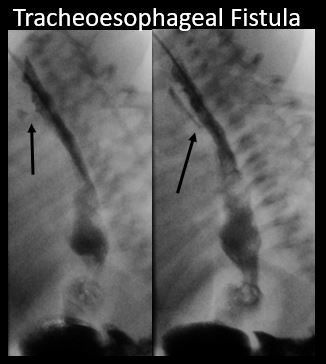

There is a tracheoesophageal fistula present.